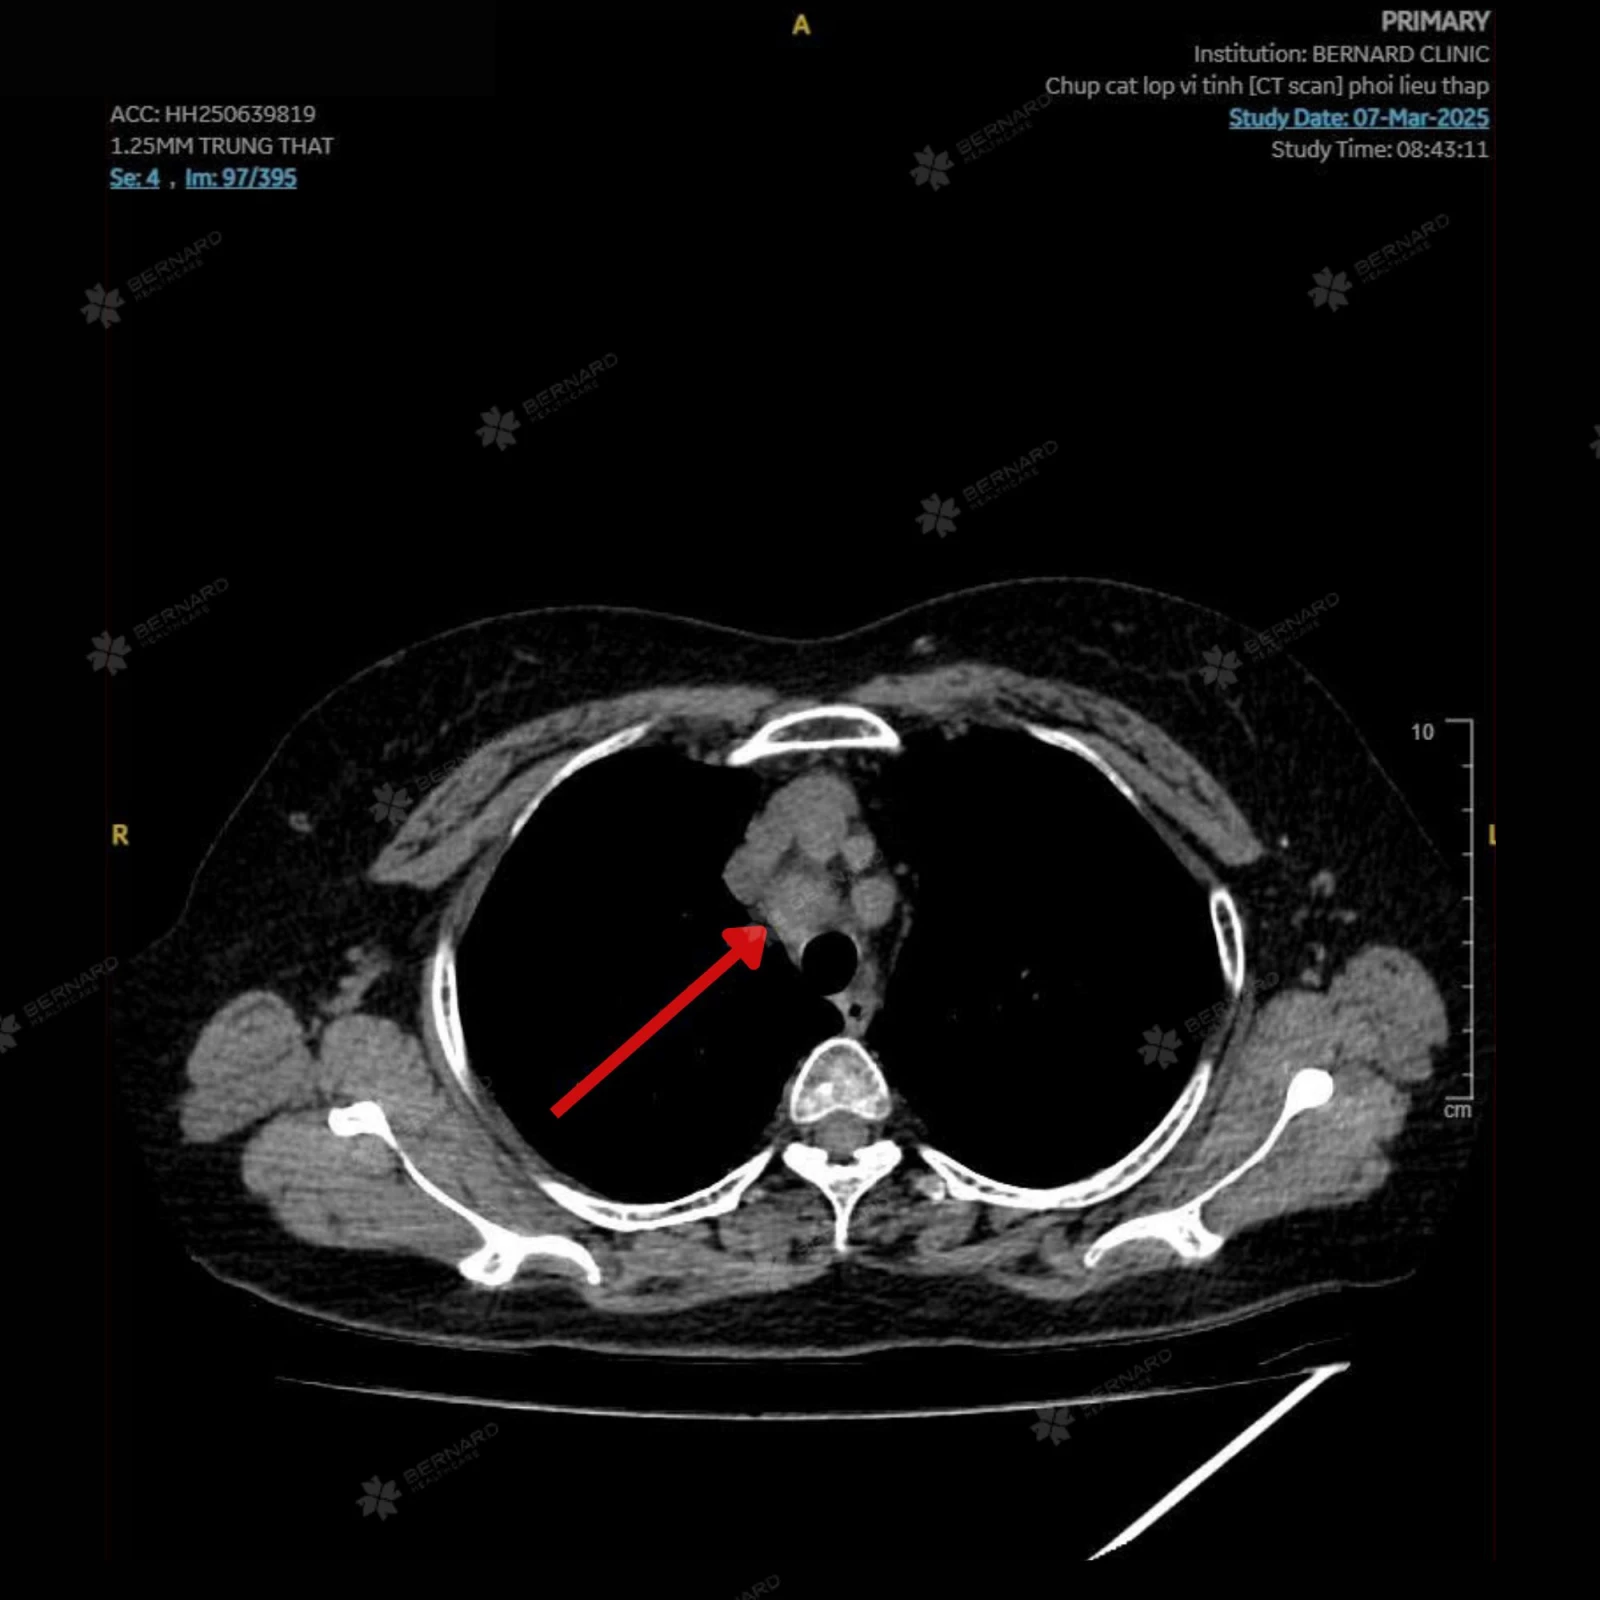

Kết quả CT Scan phổi liều thấp cho thấy một tổn thương choán chỗ thùy dưới phổi trái (S10), kích thước khoảng 1.5 x 2.5cm, đậm độ mô, bờ tua gai, kèm co kéo mô phổi xung quanh. Những đặc điểm hình ảnh này gợi ý u phổi ác tính - cần kết hợp sinh thiết để xác định chính xác bản chất của tổn thương.

Đáng chú ý, kết quả CT Scan phổi còn đồng thời ghi nhận một số hạch trung thất nghi di căn với hạch lớn nhất thuộc nhóm 2, các nốt nhỏ quanh rãnh liên thùy bé phổi phải (đường kính khoảng 3mm) và nốt dưới màng phổi thùy lưỡi (đường kính khoảng 7mm). Đây có thể là dấu hiệu tổn thương đã bước vào giai đoạn di căn hạch trung thất. Tuy nhiên, chưa ghi nhận bằng chứng lan rộng ra các cơ quan xa.